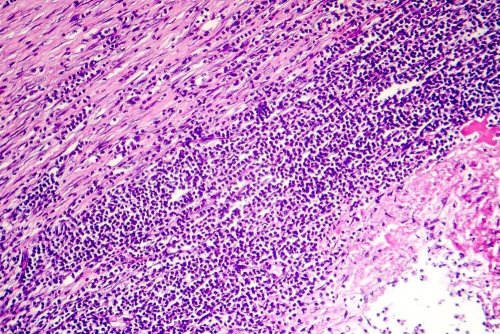

La péricardite chronique survient lorsqu’un tissu fibreux se forme autour du coeur. Ce tissu comprime l’organe et augmente la pression dans les veines qui transportent le sang jusqu’au coeur. Par conséquent, le liquide du péricarde stagne et, en essayant de sortir, il finit par s’accumuler dans d’autres parties du corps.